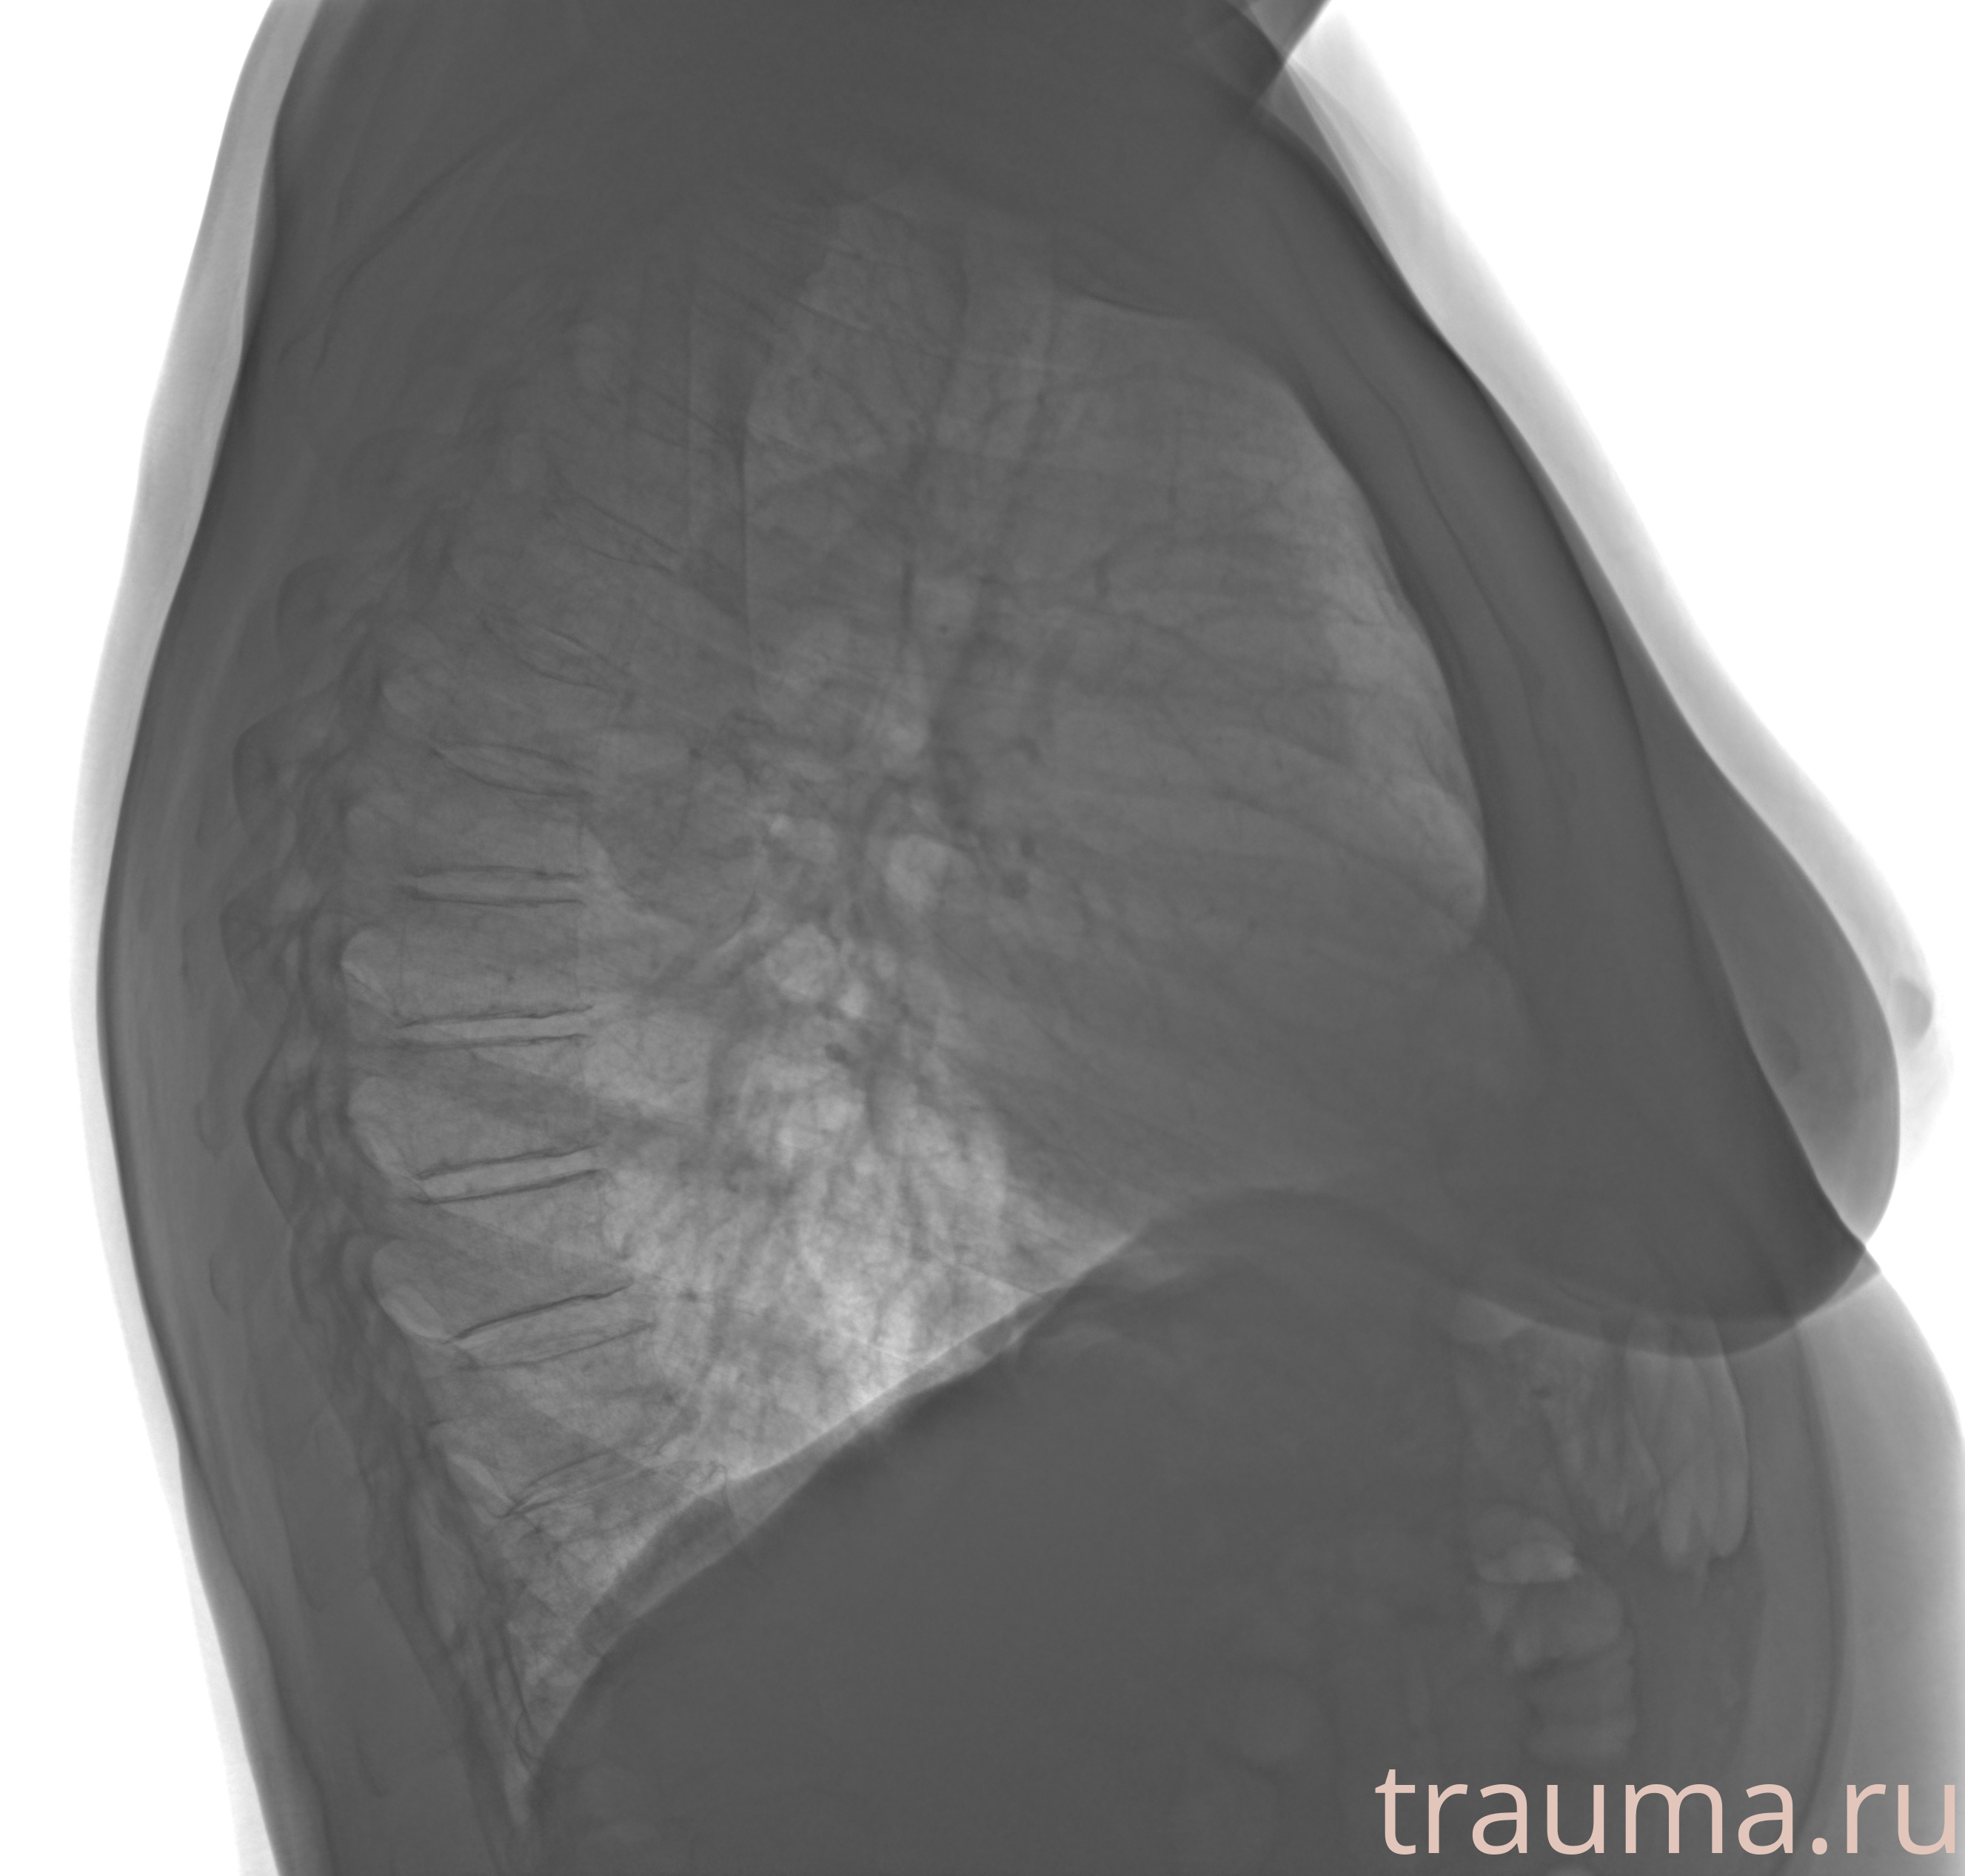

Рентген на дому: по вашему адресу приезжает врач-рентгенолог, травматолог-ортопед с мобильным рентгеновским аппаратом, проводит диагностику травмы или заболевания, делает необходимые рентгенограммы, дает рекомендации по дальнейшему лечению. Получить качественные снимки в домашних условиях возможно благодаря уникальной методике, разработанной МосРентген Центром для института  Склифосовского